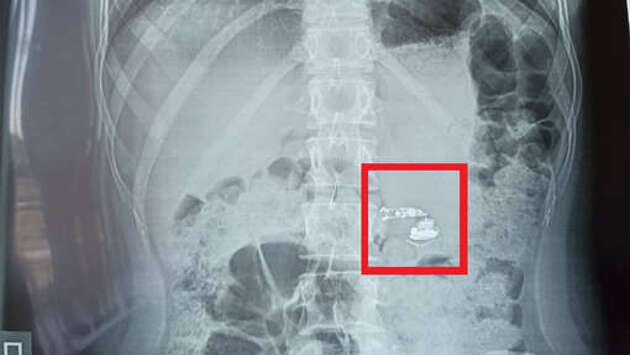

В больницу скорой медицинской помощи поступила 15-летняя пациентка, проглотившая во сне беспроводной наушник. Об этом в Telegram-канале сообщил министр здравоохранения Башкирии Айрат Рахматуллин. Школьница из Уфы проснулась ночью от резкой боли в горле, девочка вспомнила, что уснула с беспроводными наушниками и обнаружила, что одного из них на подушке нет. Испугавшись, она разбудила родителей, семья немедленно вызвала скорую помощь. На рентгеновском снимке, сделанном в больнице, медики обнаружили в кишечнике подростка инородное тело, девочку госпитализировали в хирургическое отделение. Обошлось без экстренной операции, наушник вышел естественным путем, не причинив ребенку вреда.